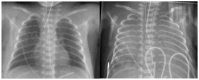

Pulmonary hemorrhage (PH) is a life-threatening complication predominantly affecting preterm infants, particularly those with very low birth weight (VLBW) and fetal growth restriction (FGR). Typically occurring within the first 72 h of life, PH is characterized by acute respiratory deterioration and significant morbidity and mortality. This review synthesizes current evidence on the multifactorial pathogenesis of PH, highlighting the roles of immature pulmonary vasculature, surfactant-induced hemodynamic shifts, and left ventricular diastolic dysfunction. Key risk factors include respiratory distress syndrome (RDS), hemodynamically significant patent ductus arteriosus (hsPDA), sepsis, coagulopathies, and genetic predispositions. Diagnostic approaches incorporate clinical signs, chest imaging, lung ultrasound, and echocardiography. Management strategies are multifaceted and include ventilatory support-particularly high-frequency oscillatory ventilation (HFOV)-surfactant re-administration, blood product transfusion, and targeted hemostatic agents. Emerging therapies such as recombinant activated factor VII and antifibrinolytics show promise but require further investigation. Preventive measures like antenatal corticosteroids and early indomethacin prophylaxis may reduce incidence, particularly in high-risk populations. Despite advancements in neonatal care, PH remains a major contributor to neonatal mortality and long-term neurodevelopmental impairment. Future research should focus on individualized risk stratification, early diagnostic tools, and optimized treatment protocols to improve outcomes. Multidisciplinary collaboration and innovation are essential to advancing care for this vulnerable population.

Figures